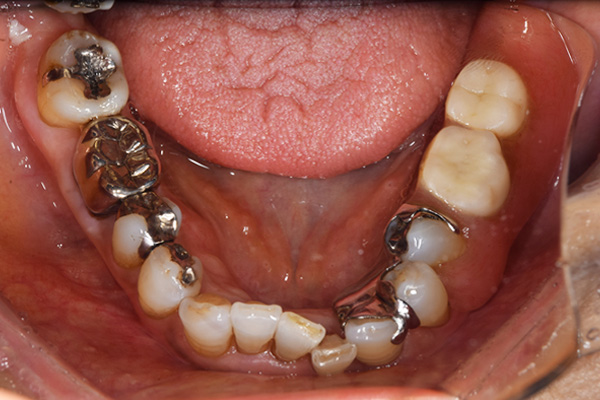

上下の入れ歯が外れやすくなったということでいらっしゃいました。 顎の骨はしっかりしていましたので、精密な型取りさえすればしっかりした入れ歯がつくれると思いました。 また下には6本歯が残っていましたが、虫歯になっている歯もありました。 かぶせ物のなかで大きな虫歯があった歯があり、1本だけ残せない状態でした。

上の入れ歯は確かに吸着は甘くなっていました。 また下の入れ歯はバネの一部が壊れており、安定感がなくなっていました。

精密な型取りの後、噛み合わせのチェックをしていきました。 かぶせ物も同時に作っていきました。

歯を並べた後、かぶせ物のフレーム作ってもらいました。先に歯を並べて理想の位置を決めておくことが大切です。

完成した入れ歯とかぶせ物です。 入れ歯への寛容度が高い患者様でしたので、 金属は使用せず、プラスチックのみで上は仕上げました。 下顎も歯は1本減ってしまいましたが、しっかり 入れ歯が維持できる様な構造にしました。

お口の中に入れた状態です。 見た目も最初とほとんど変わることなく作成できました。 維持や吸着に関しても問題ないようでした。

年齢 80歳・女性

主訴 上下の入れ歯が外れやすくなった

治療期間 3ヶ月

治療費 .メタルボンドクラウン:550,000円

.義歯:990,000円(税込、上下)

治療方針 長年使ってきた義歯の人工歯が磨耗し、臼歯部での咬合がすくなくなり、入れ歯の安定も悪くなり、あたりどころが悪くなって痛みが出ている。 そのため、入れ歯を上下作りかえる必要がある。

治療内容 過去に治療を行ったことのある歯が再度虫歯になってしまっているところがあり、すでに残せない状態にまでなっていたため、歯を一本抜歯した。 その後、かぶせ物と入れ歯を同時に作成していった。

特記事項 歯を抜いた後は、2〜3ヶ月歯ぐきの回復を待ってから入れ歯を作るため、待機期間があります。その間、古い入れ歯を調整しながらそのまま使うか、新し物をつくっておく必要があります。ただし、入れ歯は保険治療で作成する場合、6ヶ月は新しいものが作れないという決まりがあるので保険で全て作りたい場合は注意が必要です。